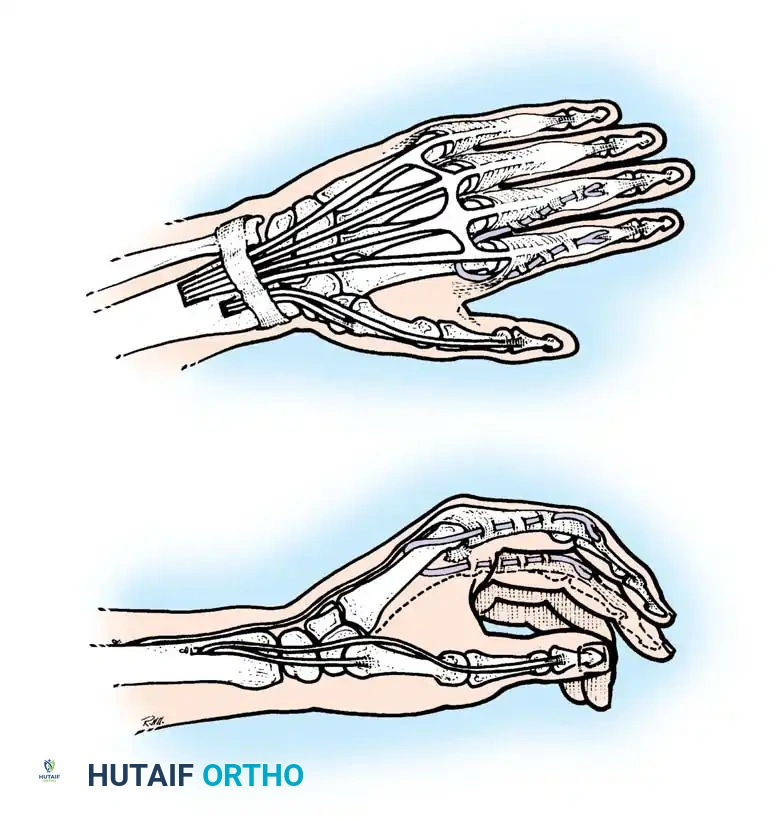

- ECRL to FDP Transfer: If the ECRB is strong enough to maintain wrist extension independently (Group 3), the ECRL can be transferred to the Flexor Digitorum Profundus (FDP) tendons to provide active, powerful finger flexion for a full grasp.

Intrinsic Balancing and the Zancolli Lasso

Tetraplegic hands are inherently "intrinsic-minus," leading to clawing of the fingers (hyperextension of the MCP joints and flexion of the IP joints). This posture defeats the tenodesis effect, as the fingers roll up into the palm rather than sweeping in a wide arc to grasp objects.

To correct this, the Zancolli lasso procedure or similar intrinsic stabilizations are performed. The Flexor Digitorum Superficialis (FDS) tendons are divided distally, looped around the A1 or A2 pulleys, and sutured back onto themselves. This creates a static volar tenodesis that prevents MCP hyperextension, ensuring that proximal pull on the FDP translates into a functional sweeping grasp.

For Hand and Wrist Reconstructions:

1. The hand is immobilized in a bulky dressing and volar splint with the wrist in neutral to slight extension, MCP joints flexed to 70 degrees, and IP joints fully extended.

2. At 3 to 4 weeks, active mobilization is commenced. Biofeedback and mirror therapy are highly effective in helping the patient achieve cortical remapping, especially when a muscle (like the BR) is asked to perform a completely novel function (like thumb flexion).